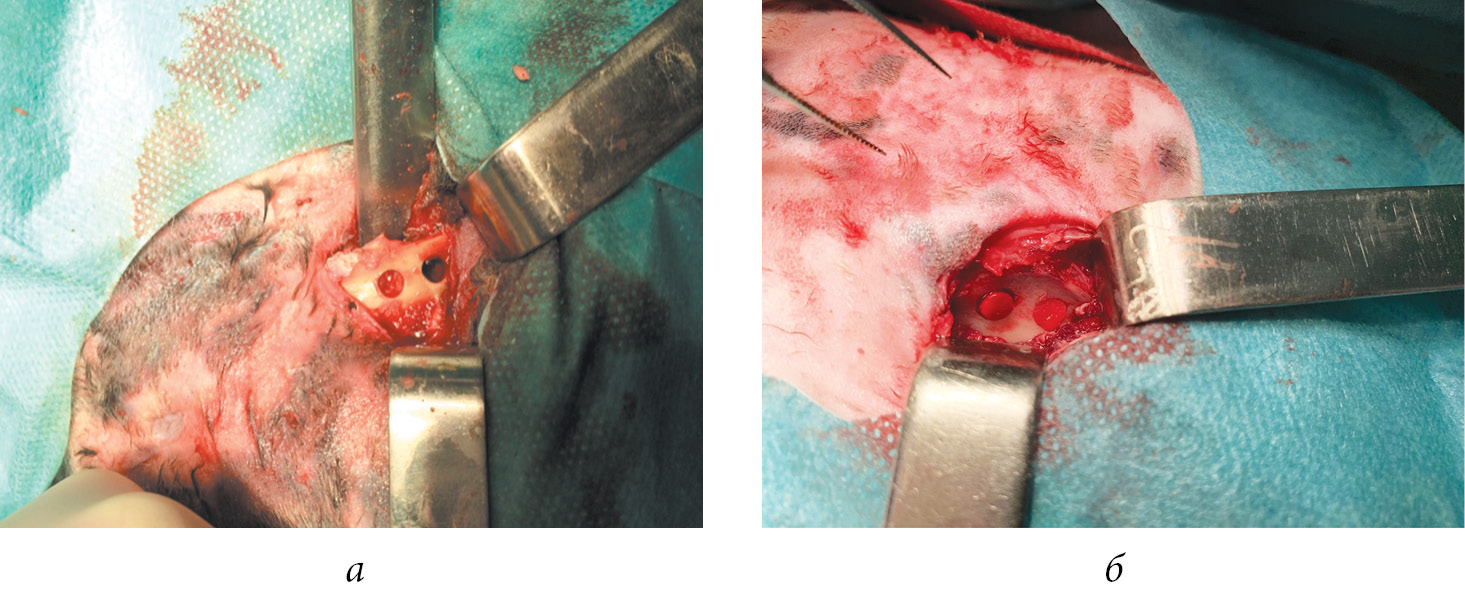

Были смоделированы повреждения подвздошной кости путем нанесения двух сквозных отверстий диаметром 5 мм, расположенных на расстоянии 1 см друг от друга (рис. 1). Общая длительность экспериментального исследования составила 28 сут. Данный срок обусловлен тем, что после 2–4 нед. резорбция костной ткани прекращается, остеокласты подвергаются апоптозу и фагоцитированию. После чего наступает короткий период покоя, когда сформированная полость покрывается остеобластами и в течение следующих 3 мес. заполняется остеоидом.

Рис. 1. Внешний вид зоны смоделированного дефекта: а — зона дефекта до имплантации исследуемых материалов; б — зона дефекта с имплантированными губчатыми материалами на основе хитозана